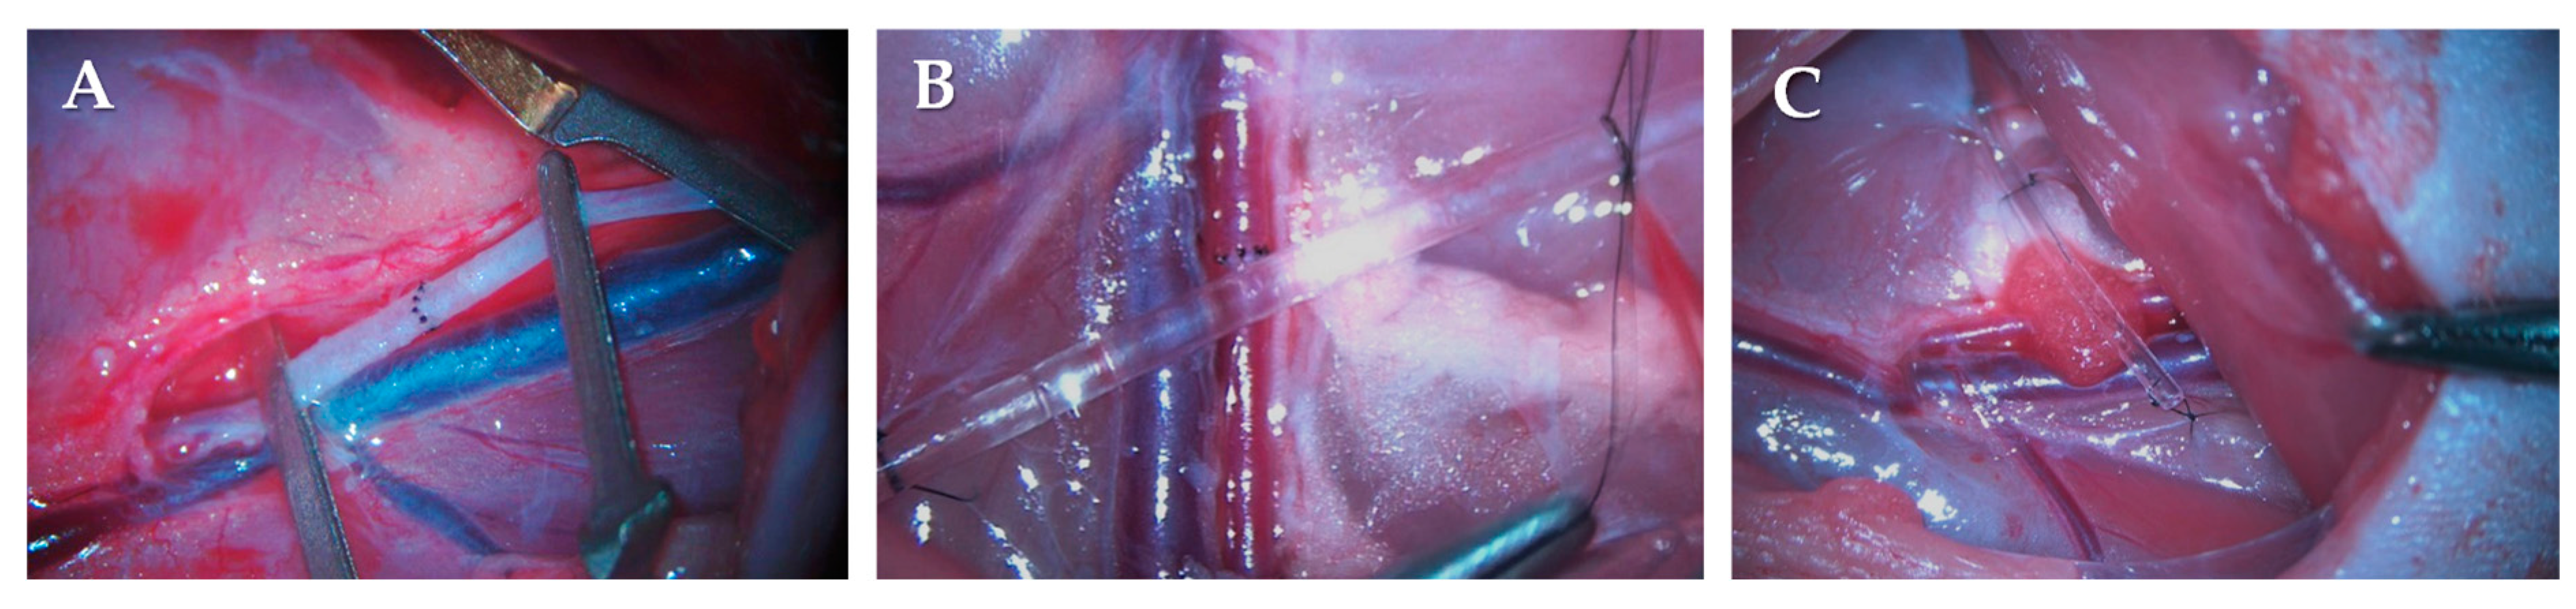

4.2. Operative Techniques, Experimental Groups and Sampling Protocol